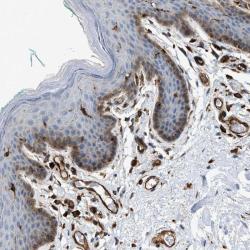

- Experimental details

- Immunohistochemical staining of human vulva/anal skin shows strong cytoplasmic positivity in squamous epithelial cells and endothelial cells.

- Validation comment

- Two independent antibodies targeting one protein yielding similar staining patterns. Staining pattern consistent with experimental and/or bioinformatic data.